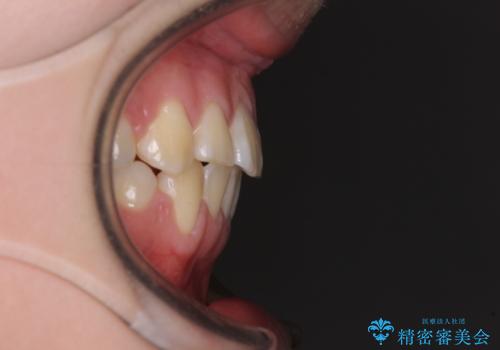

歯列はきれいに整いますが、歯肉ラインは治療前の歯肉の位置を踏襲します。

特に八重歯であった歯は歯冠が長く見えますので、改善を希望される場合には、歯肉移植術を行う必要があります。